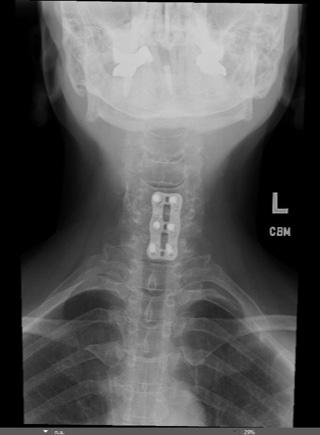

A Long-Term Risk of Cervical Arthroplasty

Cervical disc arthroplasty has emerged as an increasingly adopted alternative to anterior cervical discectomy and fusion. However, unlike fusion, which represents a biological endpoint, arthroplasty introduces a permanent mechanical interface that must remain biologically compatible with host bone for decades. As indications have expanded and younger patients receive these implants, attention has increasingly turned toward the long-term biological interaction between cervical disc prostheses and host bone. One complication that has emerged in longer follow-up studies, yet remains incompletely understood, is periprosthetic osteolysis.

Importantly, several distinct biological processes are often grouped under the term “osteolysis.” Early postoperative bone loss, often seen within the first 3–6 months, represents adaptive remodeling secondary to altered load transfer, endplate vascular disruption, or minor implant micromotion. This phenomenon is typically nonprogressive and clinically silent.1,2 True osteolysis, however, appears to represent a particle-mediated inflammatory process that may emerge years after implantation and demonstrate

progressive bone resorption at the bone–implant interface.

Device-Specific Patterns and Incidence

The incidence of osteolysis following cervical disc arthroplasty appears to vary across implant designs and has been reported to be as high as 64%, likely reflecting differences in bearing surface materials, implant architecture, and load transfer characteristics rather than a single uniform mechanism. 2 Cervical arthroplasty devices can broadly be categorized according to their articulating surfaces, including metal-on-metal, metal-on-polymer, and viscoelastic or polymer-core constructs, each of which introduces distinct wear characteristics that may influence the long-term biologic response of the vertebral body. Greater variability exists when examining individual implants. For example, the M6-C artificial disc manufactured by Orthofix, which utilized an ultra-high-molecular-weight polyethylene core, was associated with a 34% revision rate at an average of 67 months (about 5 and a half years) owing to wear-related osteolysis in one series.7 Reports exist describing polyetheretherketone

(PEEK)-on-ceramic design wear and osteolysis, histologically linked to an inflammatory process. 8 Such analyses have suggested PEEK, titanium, and zirconia debris are linked to inflammatory reactions that may contribute to osteolysis. Metal-on-metal devices have shown radiographic bone loss as high as 52.8%, although most cases are nonprogressive. 9

These findings underscore that osteolysis is not uniform across designs and may reflect differences in bearing materials, fixation strategy, and load transfer. Further, many radiographic changes have gone undiagnosed as patients remain asymptomatic, and there has been inconsistent reporting differentiating osteolysis from other processes such as stress shielding. 9

Clinical Presentation and Diagnostic Challenges

Cervical osteolysis often is asymptomatic early on, thus delaying diagnosis.7,11 Radiographically, osteolysis may present as progressive radiolucent zones surrounding the implant endplates, focal vertebral body cavitation, or erosion extending into the posterior vertebral body. CT often provides superior characterization of bone loss.

Symptomatically, patients may present progressive neck pain or neurologic change related to implant subsidence or device migration. Such delays in diagnosis often lead

to substantial bone loss limiting the ability of revising to another arthroplasty construct and require a fusion with or without a corpectomy.7